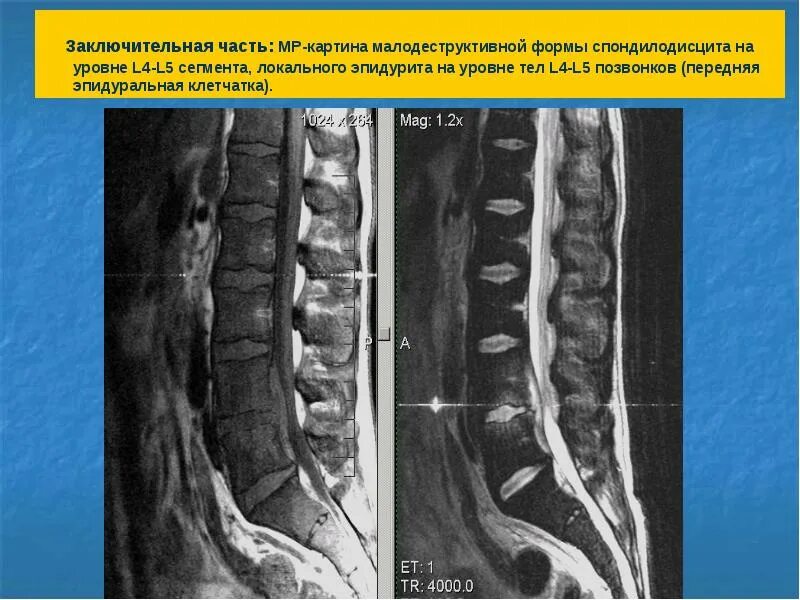

L5 s1 форум